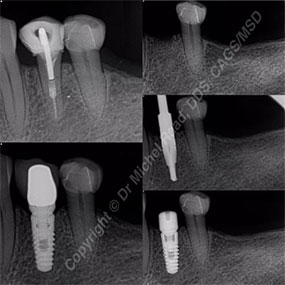

See a dentist in San Ramon, CA, for checkups, cleanings, fillings, crowns, and night guards that protect your bite. Our cosmetic services include whitening, bonding, and smile balancing that looks natural and confident. A dentist in San Ramon, California treats gum concerns, repairs chips or fractures, and offers same-day emergency visits when available. If dental anxiety has held you back, your dentist in San Ramon, California can provide nitrous or other sedation options to help you relax. Missing teeth affect how you eat, speak, and smile. After a thorough exam, a dentist in San Ramon, California reviews choices such as single dental implants, implant bridges, and implant-retained dentures. With 3D planning and a cleanable design, your dentist in San Ramon, California aims for strong chewing, stable comfort, and lasting value.